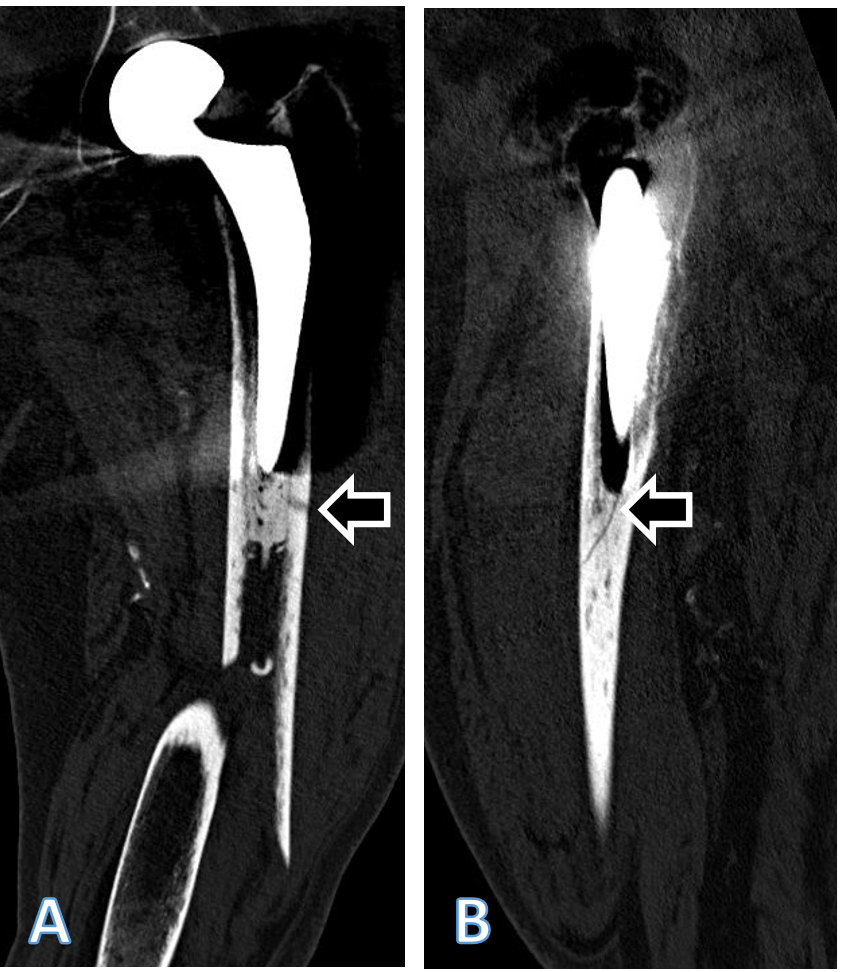

Figure 2: Coronal (a) and sagittal (b) computed tomography (CT) scan reconstructions of the left femur of the patient described, showing the periprosthetic fracture. The extension of the fracture into the lateral cortex at the level of the tip of the stem arrow in (a) as well as a fracture of the cement distally to the tip of the stem arrow in (b) are visible. Both fracture extensions had been missed by the treating team. Accordingly, and considering the line-to-line principle of cementation of the affected stem, the fracture should be classified at least as Unified Classification System Type B2, if not B3, and not as a type C. The sublux-ated appearance of the head of the femoral head prosthesis is an artifact due to movement of the patient during the CT examination.

As the treating team considered the stem to be stable, with a fracture evaluated as being located distally to the area of fixation (Unified Classification System [UCS] Type C) [17], plate fixation was chosen. Open reduction and internal fixation of the fracture was performed through a subvastus approach, with reduction and fixation by a cable cerclage (Cable System 1.7 mm, DePuy Synthes, Zuchwil, Switzerland) and application of a lateral neutralization plate (non-contact bridging [NCB] Periprosthetic Femur Plate System 18 hole, Zimmer Biomet, Zug, Switzerland), fixated distally with screws and along the level of the stem with further cable cerclages (Cable System 1.7 mm). Postoperatively, the patient was mobilized in a wheelchair, as full weight-bearing was not recommended and as it was not possible to implement partial weight-bearing. Wound healing was uneventful. The radiological follow-up after 8 weeks showed intact material without evidence of loosening (Fig. 1c). Mobilization under full weight-bearing with support by physical therapy was then attempted. Four months postoperatively, the radiological follow-up showed a general atrophy of the cortical bone, which was accentuated at the lateral cortex, underneath the plate (Fig. 1d). Mobilization was hampered due to thigh pain, which had been interpreted to be caused by muscle atrophy. Thus, further physical therapy was recommended. As the impaired mobility caused difficulties attending consultation at the hospital, no further follow-up visits were planned. Due to increasing thigh pain, the patient was readdressed for evaluation by her general practitioner 4 years after the operative treatment of the PPF. Not having been mobilized outside a wheelchair in the meantime, the patient showed bilateral hip and knee flexion contractures. Consequently, she was unable to stand, disregarding the issue of thigh pain. Radiologically, there was now pronounced atrophy of the cortical bone of the femur, particularly of the lateral cortex under the plate (Fig. 1e). An infection was considered unlikely, as there was no pain at rest, as the soft tissues were inconspicuous, as the fracture had healed, and as there were no general symptoms. A single-photon emission computed tomography (CT) showed avascular areas of cortical bone underneath the plate (Fig. 3). The CT better illustrated a general atrophy of the femur with thinning of the bone cortex in comparison to the contralateral femur (Fig. 4 and 5). There was, however, no sign of loosening of the stem. Considering comorbidities, very limited potential for recovery, and the patients’ desire for no more surgery, the option of a revision was rejected, accepting the present situation. The patient died 7 months later.

The treatment of a PPF with internal fixation is an established surgical treatment option [8,19]. Whether internal fixation is adequate for treatment of PPF of the femur depends on the stability of the stem, respectively, the fracture pattern and localization, as well as potential stability after fixation [2]. The general condition of the patient may also be part of the decision-making process, internal fixation being potentially less invasive than stem revision. Thus, internal fixation may be an acceptable option in case of severe comorbidities and limited functional requirements, even if otherwise, stem revision would be the treatment of choice from a mechanical point of view [9,19,20,21,22,23,24]. In the presented case, the fracture had been classified by the treating team as a type C fracture, according to the UCS classification [17]. However, a more detailed analysis of the CT scan showed an extension of the fracture into the lateral cortex at the level of the tip of the stem, as well as a fracture of the cement at the same level (Fig. 2). Cement fixation of the stem design used in this case was based on the line-to-line concept [25,26,27]. An interruption of the connection between the stem and the cement leads to an unstable situation with this kind of cementation principle [2,27]. Therefore, the fracture should have been classified correctly as a type B2, possibly even B3, considering the poor bone quality. Low functional demands were probably decisive regarding the outcome of the stem, as the patient never became ambulatory again. Thorough radiologic work-up of PPF, including evaluation of the zone of fixation of the affected implant, is recommended before decision-making [20]. When opting for internal fixation, it is recommended to apply a plate spanning the entire length of the femur [8]. Various implants are available for the treatment of PPF. Universal plates, such as the standard large fragment LCP (DePuy Synthes), which is also available curved, can be used. Alternatively, anatomically pre-shaped plates are available from different manufacturers, such as the NCB plate (Zimmer Biomet), which was applied in this case. The latter plate possesses some specific design features that need consideration when employing it for internal fixation of PPF. A relevant proportion of the blood supply to the bone of the diaphysis originates from the periosteum [12,28]. Implants used for internal fixation, such as conventional plate-screw-constructs, can impede blood supply by exerting direct pressure on the bone, consecutively increasing the risk of local bone necrosis and non-union [11,12,13,15,29]. Undercuts have been incorporated into plate designs to reduce contact with the underlying bone and preserve blood supply [11,12,13,15,29,30]. In contrast, the undersurface of the NCB plate lacks such indentations (Fig. 7).